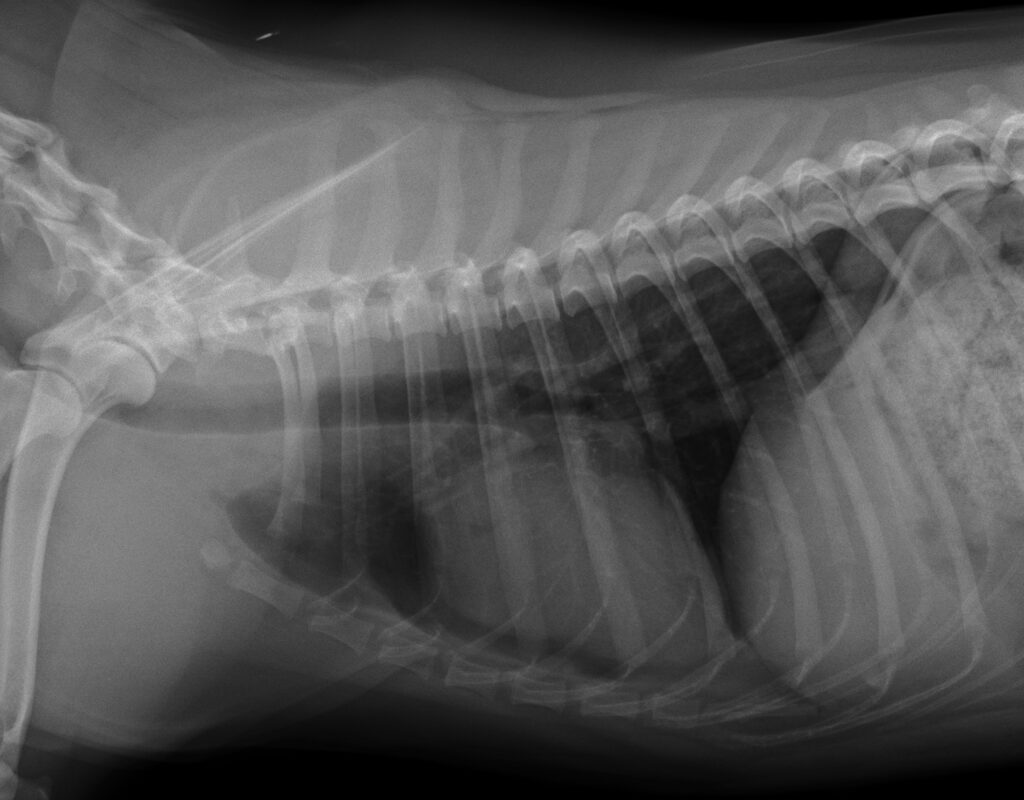

心臓尾側にmass様の陰影を認める。

エコー検査、CT検査にて胸腔内(心臓尾側)に肝臓実質(方形葉)が脱出。